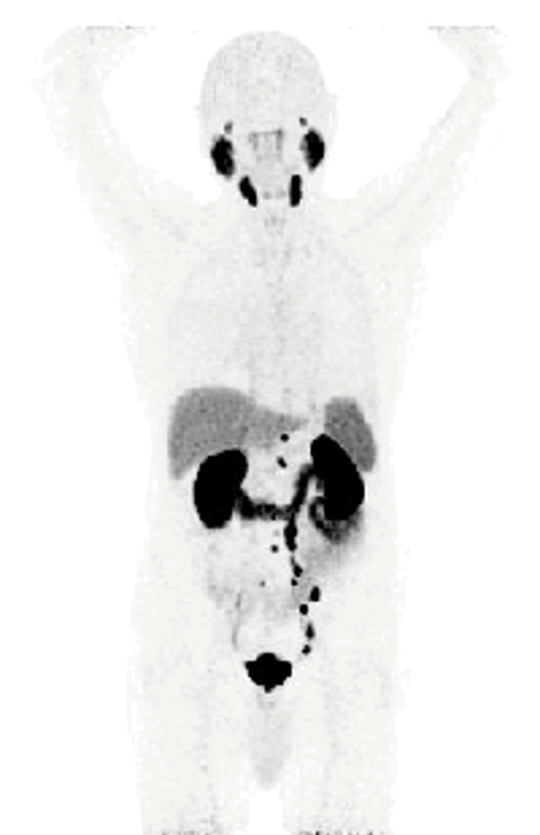

Mit der PSMA-PET/CT steht uns in der Klinik für Nuklearmedizin am UKS ein bildgebendes Untersuchungsverfahren zur Verfügung, mit dem wir in der Lage sind, insbesondere Prostatakrebs aufzuspüren und dessen Ausbreitung im Körper zu beurteilen. PSMA steht für „Prostata-spezifisches Membran-Antigen“, ein Eiweiß-Molekül, das überwiegend auf der Oberfläche von Prostatakrebszellen zu finden ist. Bei der PET/CT kombinieren wir zwei Untersuchungen miteinander: die Positronen-Emissions-Tomografie, bei der wir Funktionen auf molekularer und zellulärer Ebene betrachten können, und die Computertomografie für anatomische Bilder.

Bei der PSMA-PET/CT wird ein Radiopharmakon namens Gallium-68-PSMA-Ligand verwendet, das an das prostataspezifische Membran-Antigen (PSMA) auf der Oberfläche von Tumorzellen bindet. Dies ermöglicht eine Bildgebung mit sehr hohem Kontrast, wodurch selbst kleinste Tumorabsiedlungen entdeckt werden können, die anderen bildgebenden Verfahren entgehen könnten. Laut aktueller Forschung ist die PSMA-PET/CT anderen Methoden wie der Computertomografie und der Knochenszintigrafie beim Aufspüren von Metastasen beim Prostatakrebs überlegen.

Die Strahlung des Gallium-68 ermöglicht es dem PET/CT-Scanner, die Anreicherungsorte im Körper zu lokalisieren und bildlich darzustellen. Um die gefundenen Herde genau anatomischen Strukturen (wie Lymphknoten und Weichteilen) zuordnen zu können, wird ergänzend eine Computertomografie (CT) durchgeführt. Die Bilder der 68Ga-PSMA PET und der CT werden übereinandergelegt und gemeinsam ausgewertet. So können die in der PET gefundenen Herde präzise den jeweiligen anatomischen Strukturen zugeordnet werden, was eine genauere Diagnose ermöglicht.